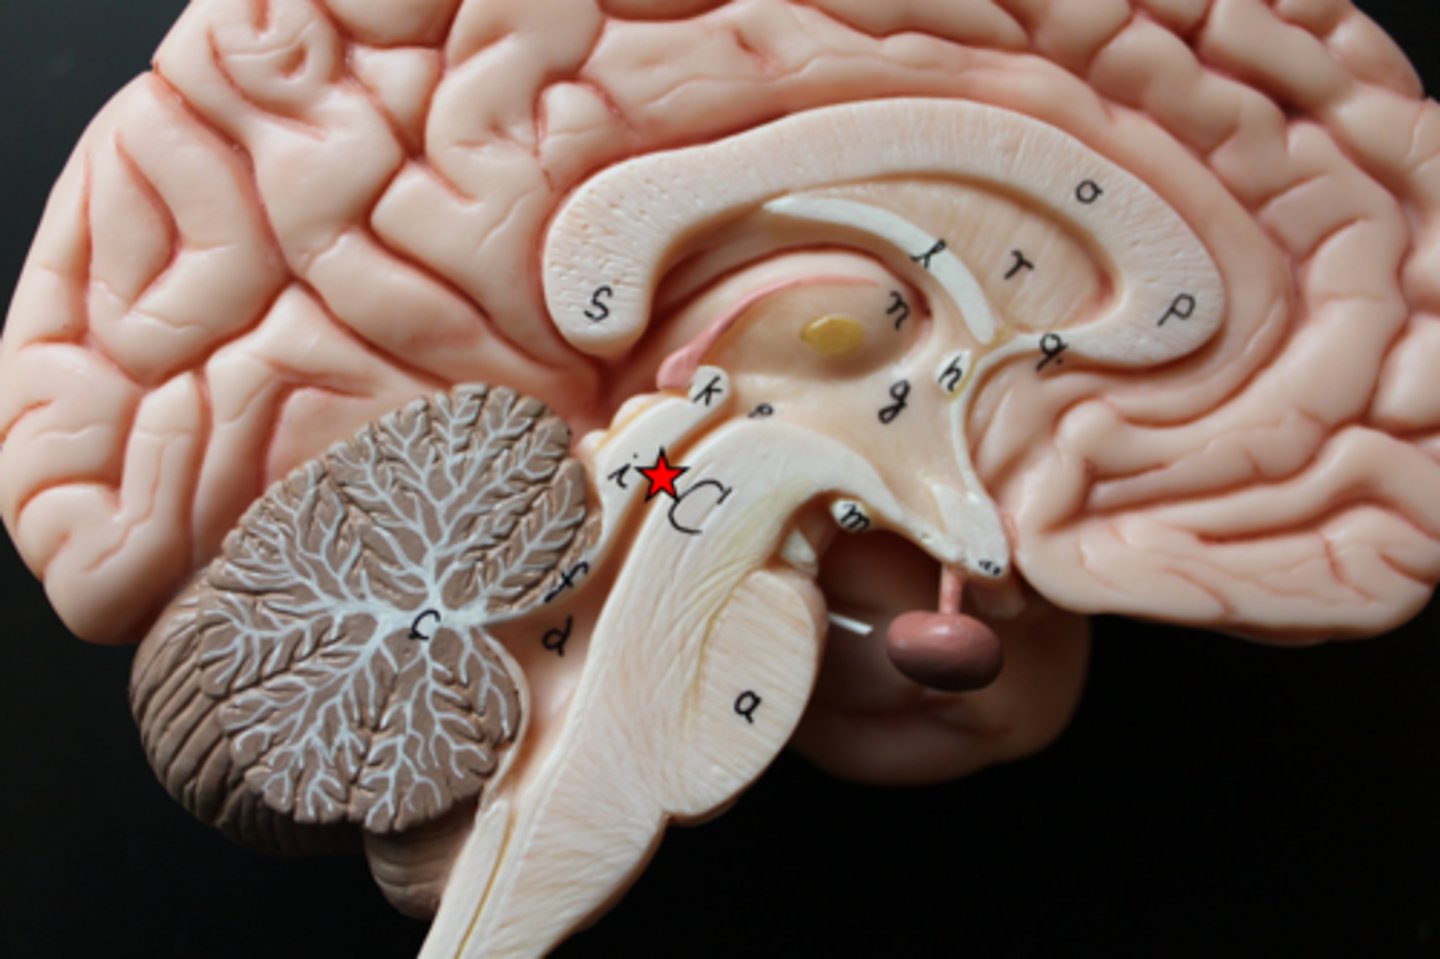

Diencephalon

thalamus, hypothalamus, epithalamus

thalamus

the brain's sensory switchboard, located on top of the brainstem; it directs messages to the sensory receiving areas in the cortex and transmits replies to the cerebellum and medulla

hypothalamus

A neural structure lying below the thalamus; it directs several maintenance activities (eating, drinking, body temperature), helps govern the endocrine system via the pituitary gland, and is linked to emotion and reward.

epithalamus

Contains pineal body. Involved in olfactory senses and sleep/wake cycle- melatonin

cerebellum

the "little brain" at the rear of the brainstem; functions include processing sensory input and coordinating movement output and balance

arbor vitae

white matter of the cerebellum

outer gray matter of cerebellum

cerebellar cortex

vermis

Connects the two hemispheres of the cerebellum

brainstem

the oldest part and central core of the brain, beginning where the spinal cord swells as it enters the skull; the brainstem is responsible for automatic survival functions

mid brain, pons, medulla oblongata

midbrain

A small part of the brain above the pons that integrates sensory information and relays it upward.

pons

A brain structure that relays information from the cerebellum to the rest of the brain

medulla oblongata

Part of the brainstem that controls vital life-sustaining functions such as heartbeat, breathing, blood pressure, and digestion.

cerebrospinal fluid (CSF)

plasma-like clear fluid circulating in and around the brain and spinal cord

CSF circulates through

lateral ventricles to third ventricle to cerebral aqueduct to fourth ventricle to subarachnoid space and central canal of spinal cord

lateral ventricle

one of the two ventricles located in the center of the telencephalon

third ventricle

the ventricle located in the center of the diencephalon

cerebral aqueduct

connects the third and fourth ventricles

fourth ventricle

the ventricle located between the cerebellum and the dorsal pons, in the center of the metencephalon